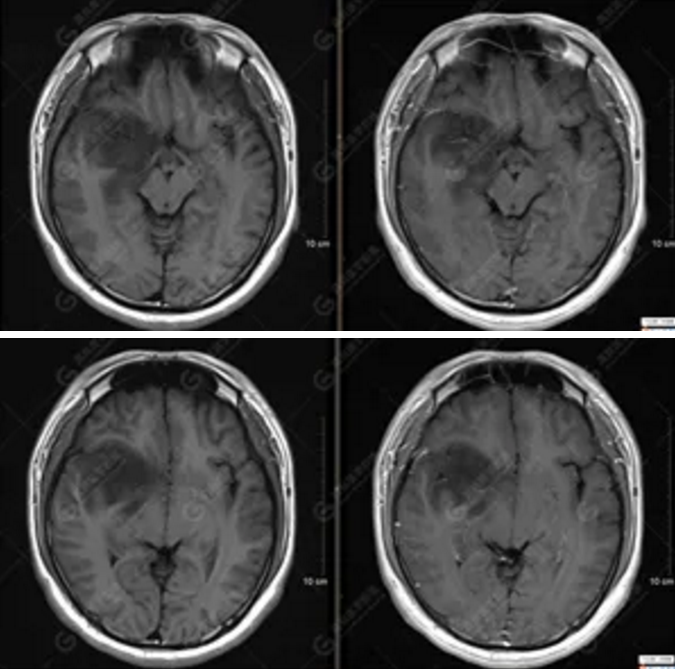

MR影像圖

【MRI平掃及增強(qiáng)檢查所見(jiàn)】右側(cè)額顳島葉、右側(cè)海馬及右側(cè)基底節(jié)區(qū)見(jiàn)一團(tuán)塊狀異常信號(hào)影,累及右側(cè)下丘腦及視交叉,大小約5.1cm×4.5cm×4.3cm,呈長(zhǎng)T1長(zhǎng)T2信號(hào),F(xiàn)LAIR序列呈等、稍高信號(hào),DWI序列呈稍高信號(hào),ADC圖高信號(hào),增強(qiáng)后無(wú)明顯強(qiáng)化;病灶周?chē)?jiàn)片狀長(zhǎng)T1長(zhǎng)T2水腫信號(hào)影,F(xiàn)LAIR序列呈高信號(hào),病灶內(nèi)見(jiàn)右側(cè)大腦中動(dòng)脈穿行。余腦實(shí)質(zhì)內(nèi)未見(jiàn)局灶性信號(hào)異常,增強(qiáng)后未見(jiàn)異常強(qiáng)化。右側(cè)側(cè)腦室輕度受壓,余腦室、腦池大小、形態(tài)均正常,中線(xiàn)結(jié)構(gòu)居中